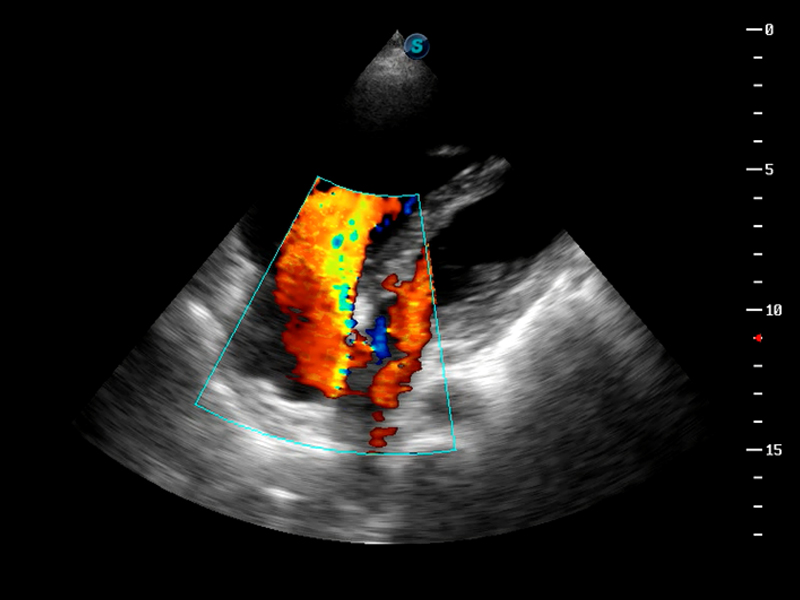

S9便携式彩色多普勒超声诊断仪是竞技宝(JJB)官方网站研发的高端便携彩超设备,外观设计新颖、产品性能卓越。S9在便携超声领域采用了突破传统的触摸屏交互设计,并以先进的软件硬件技术和设计理念,为您带来清晰的图像质量、稳定的工作性能和便捷的操作体验。

TDI组织多普勒成像

AutoC智能血流追踪